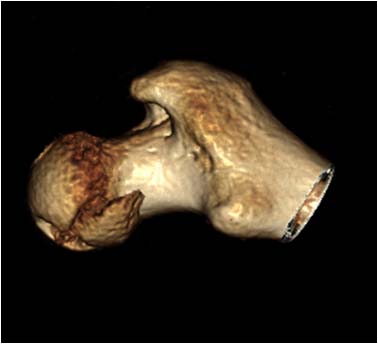

суставных щелей в сравнении с неповрежденной стороной. Сделали КТ,

которое подтвердило наличие внутрисуставного фрагмента задней стенки

вертлужной впадины и перелом нижне-медиального сегмента головки со

смещением (Pipkin IV).

Обращал на себя внимание значительный дефект хряща головки бедра в

нагружаемой зоне (как результат контакта головки с внутрисуставным

фрагментом). Глубина повреждения хрящевого покрытия в центральной части

дефекта достигает кости. Ничего не делали, расcчитывая на замещение